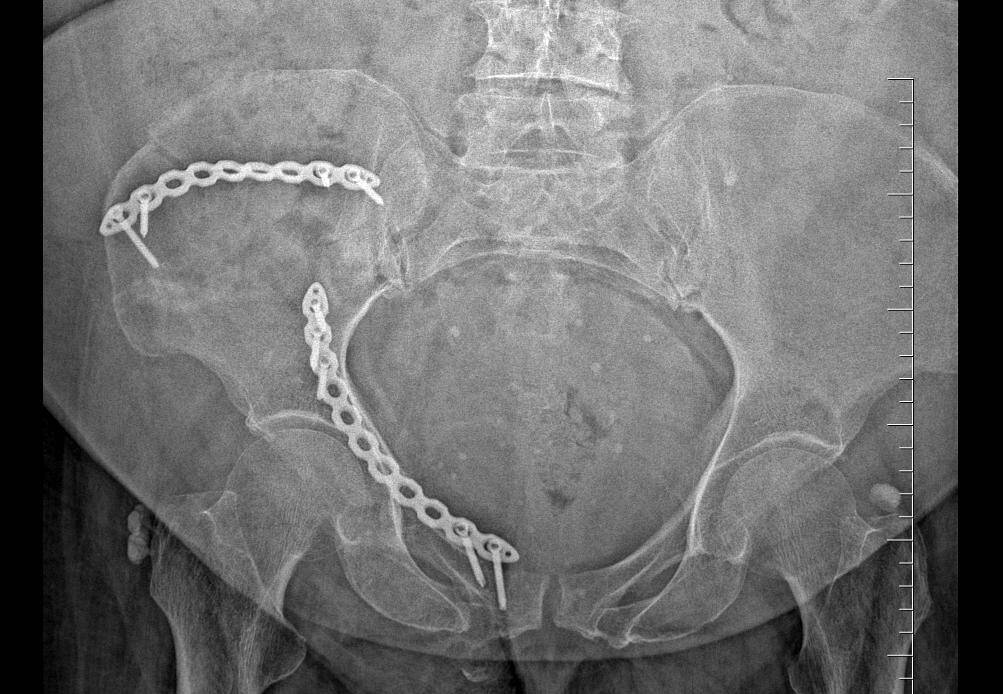

Kırılan leğen kemiğini 20 halkalık zincirle birleştirdiler